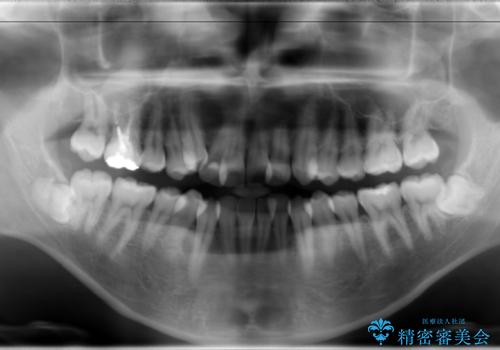

骨格的に上顎骨が小さいために相対的に下顎骨が前に出ていたため、歯の傾きなど理想的な仕上がりが難しく、外科矯正ではなく歯列矯正の場合はカモフラージュ矯正になること説明の上、矯正治療を進めることになりました。

上顎は左右5番抜歯、下顎は左右4番抜歯しています。

途中までは下顎は全体にワイヤーをはらずに、セクショナルワイヤーにて治療を進めています。

上顎は最初から全体にワイヤーをはっていましたが、上顎前歯部の歯肉退縮のリスクが高そうだったために、途中まで下顎と同じくセクショナルワイヤーで進めています。